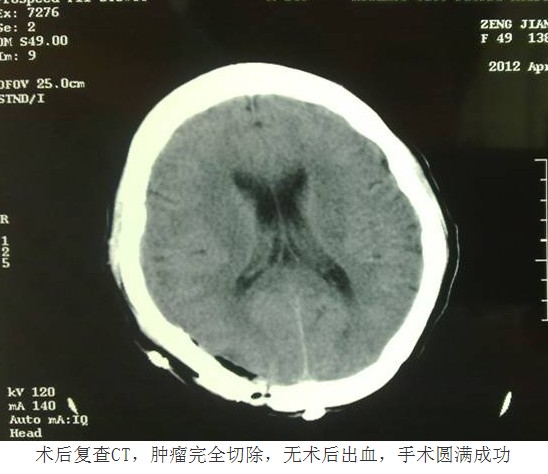

凭借先进的技术与丰富的经验,换来的是患者快速的康复。由于手术核心部分均是在显微镜下操作,在完整切除肿瘤的同时,最大限度减少了对周围正常脑组织的损伤,术中出血很少,因此术后患者没有出现任何中枢感染、神经功能障碍等异常情况,复查头颅CT显示肿瘤完整切除,无术后出血。术后第十天,患者即痊愈出院。